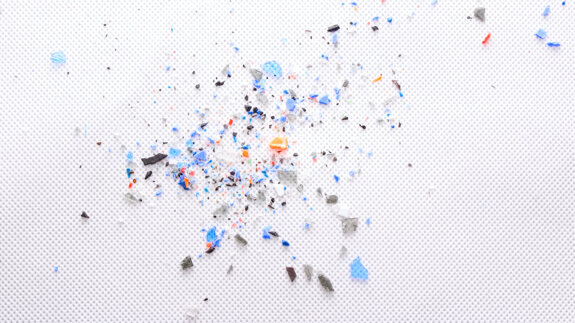

Prawidłowo opracowana tkanka jest mikroporowata. Makroskopowy obraz ubytku opracowanego przy pomocy wiertła dentystycznego ukazuje gładki wygląd ścian, w odróżnieniu do obrazu po ablacji laserem Er:YAG, gdzie brzegi i ściany ubytku są nieregularne.13 Mikroskopowo po preparacji laserowej obserwujemy charakterystyczne kratery o gładkich ścianach, bez obszarów zwęglenia czy nadtapiania szkliwa i zębiny oraz bez warstwy mazistej. Powierzchnia szkliwa uzyskuje mikroretencyjną strukturę, pryzmaty szkliwne są jasno rozpoznawalne, kanaliki zębinowe są otwarte i wolne od warstwy mazistej, co pozwala na głęboką penetrację materiału wiążącego i wzmacnia adhezję materiału kompozytowego do ścianek ubytku.14-16